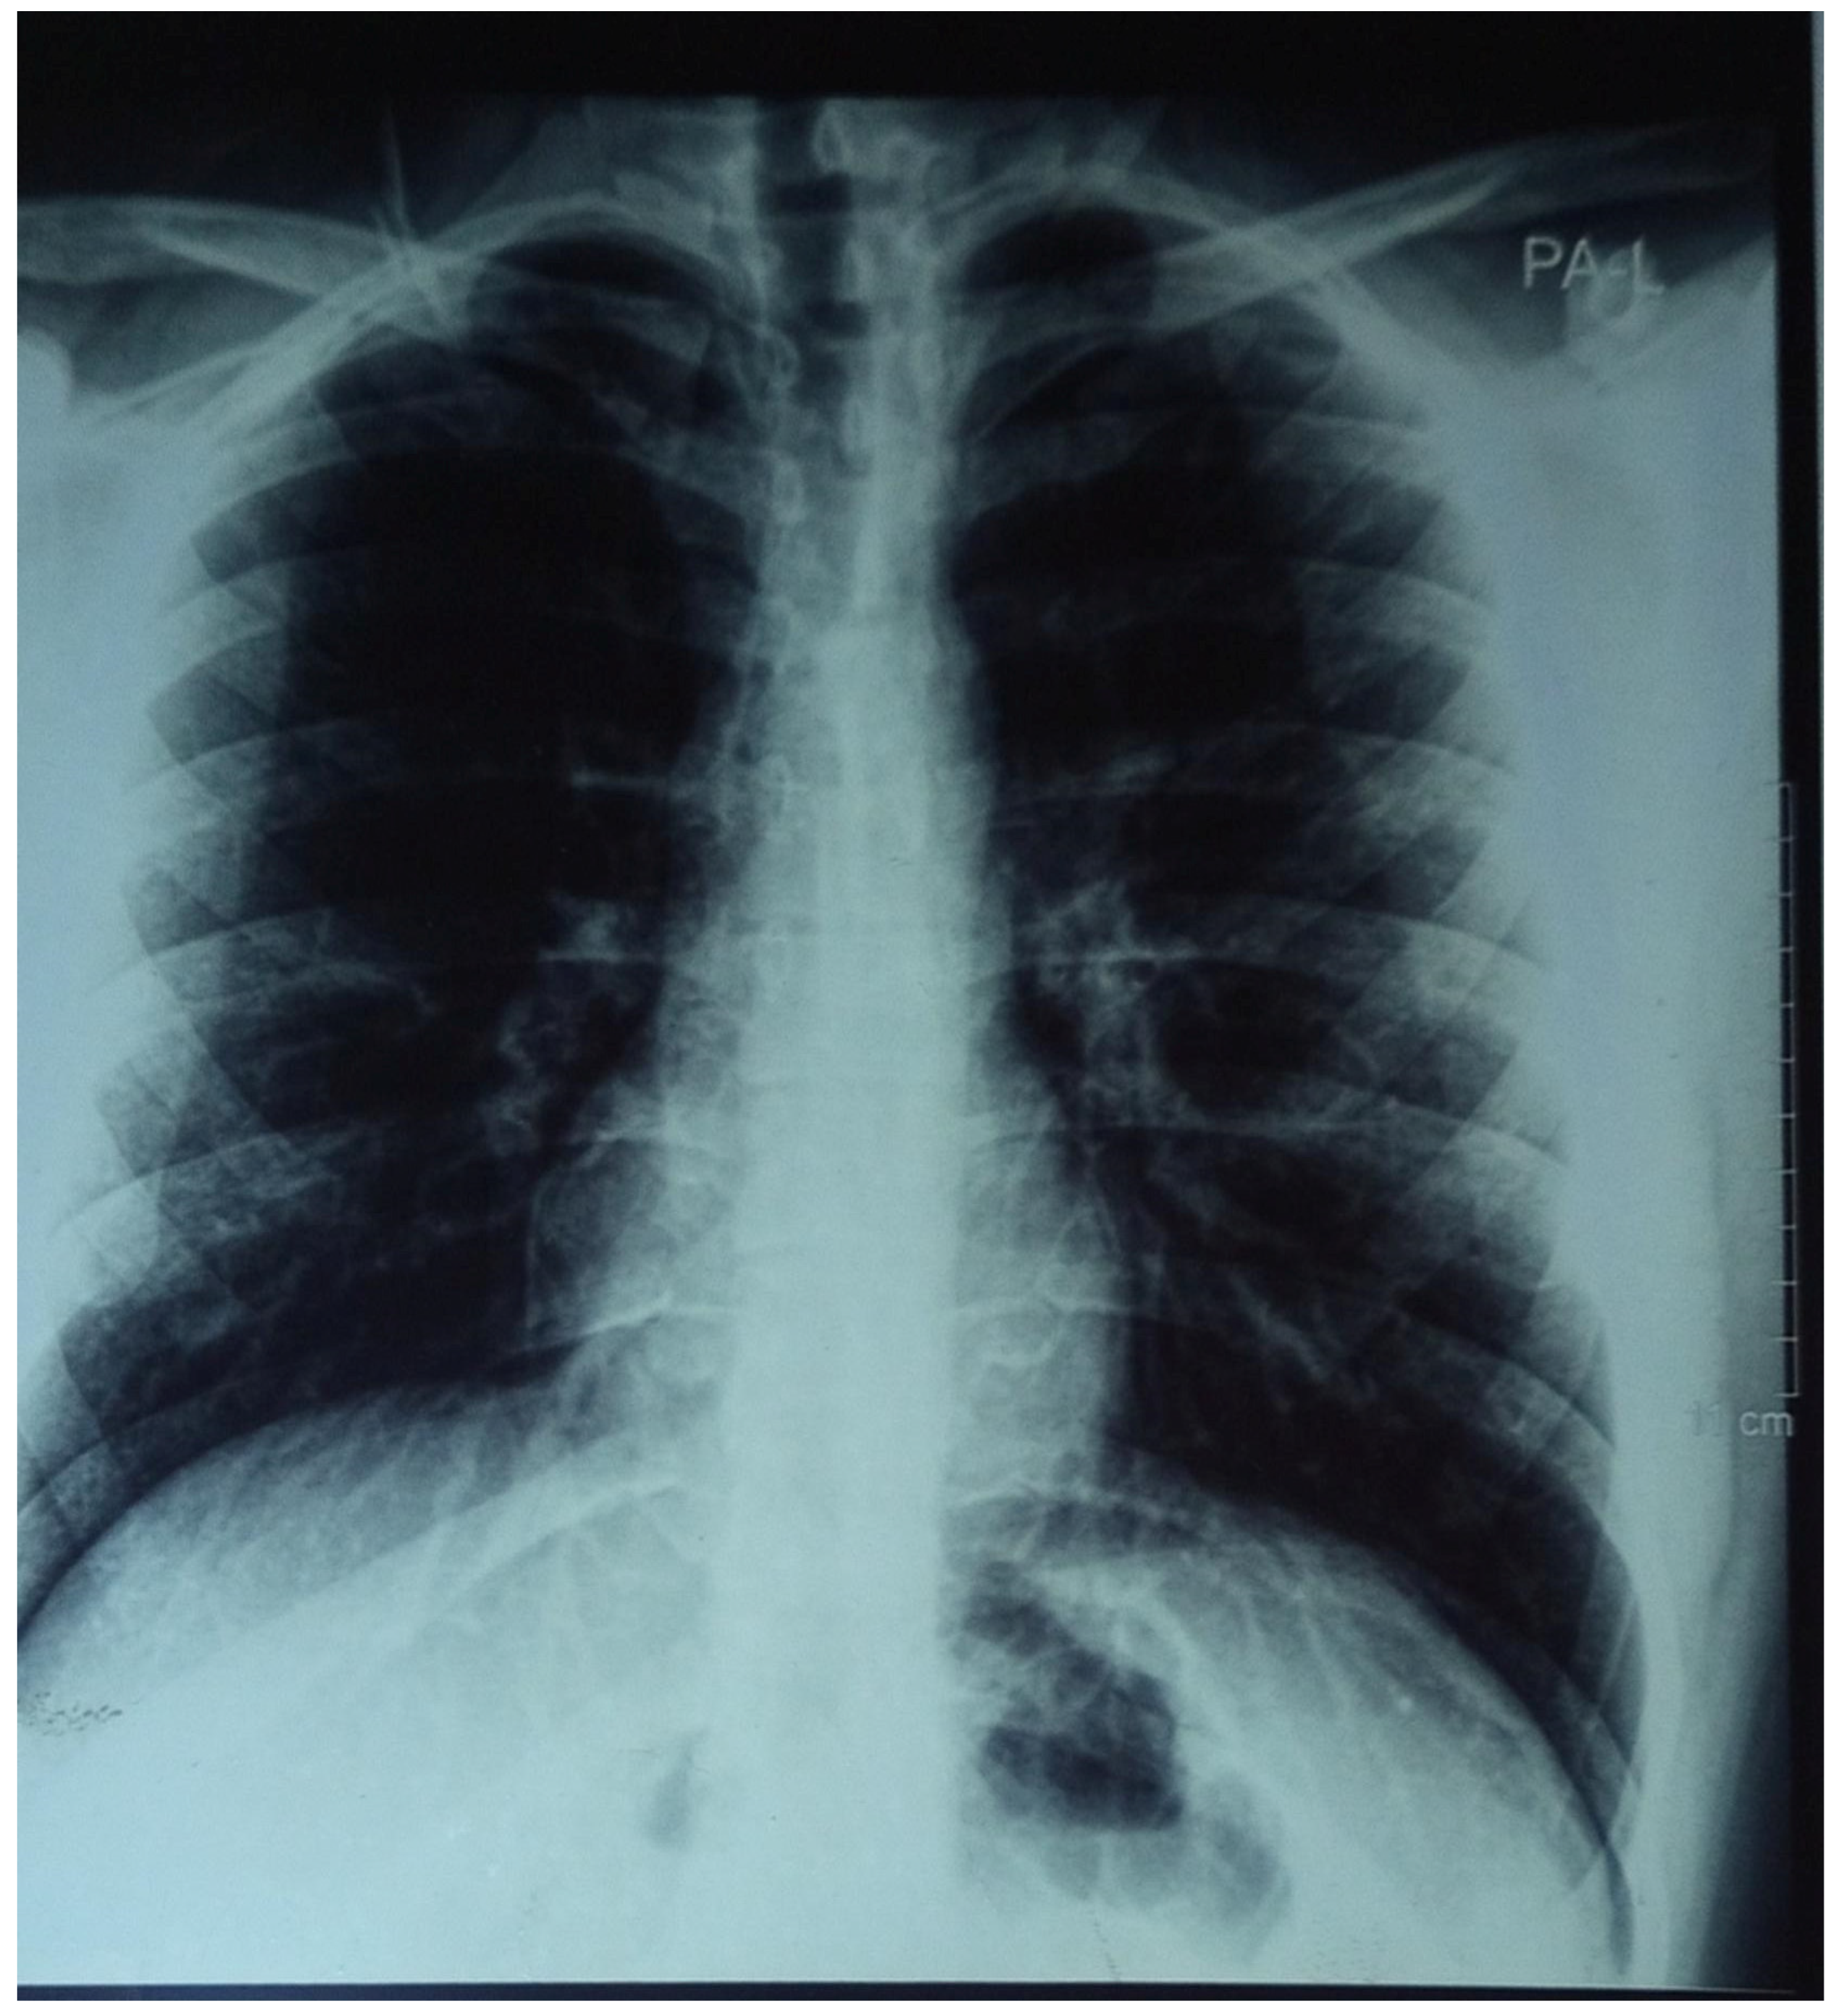

- Chest X-ray: normal ( see Figure 1)